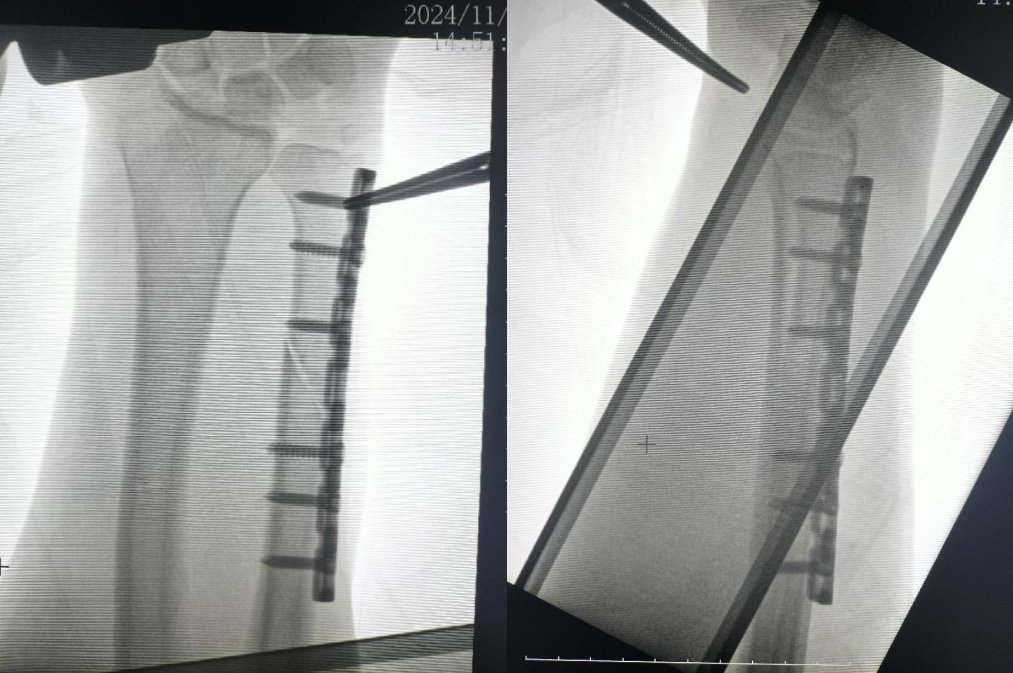

患者许先生,48岁,半年前因不慎摔伤导致左腕部骨折。在外院接受外支架固定手术,术后五周拆除外固定支架。然而,康复之路并不平坦,术后效果欠佳,近日,患者出现了左腕部酸痛不适的症状。前来湖州邦尔骨科医院关节外科,找到李龙付主任就诊。进一步检查后,患者被诊断为左腕月骨缺血性坏死、三角纤维软骨损伤、舟骨小片缺血灶以及尺骨茎突撕脱骨折。

术前查示:左腕月骨缺血性坏死,左腕三角纤维软骨损伤;左腕舟骨小片缺血灶;左尺骨茎突撕脱骨折。

在全面评估了患者的病情后,李龙付主任团队迅速展开术前规划,精心制定了手术治疗方案。手术中,医生采用了腕关节镜技术,进行了坏死软骨的清理,三角软骨的修复,以及尺骨短缩内固定术。手术成功实施,目前活动及功能恢复良好。

腕关节镜术后